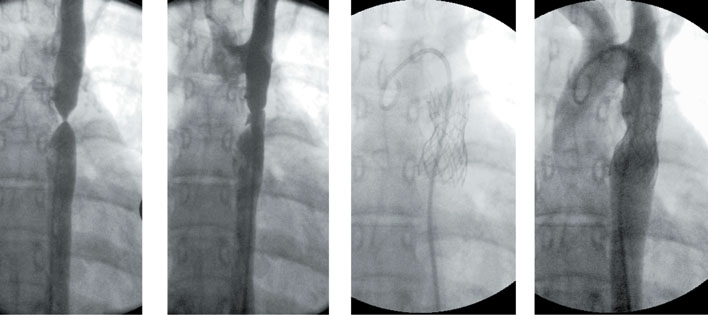

Chest X-ray and ECG may help in the diagnosis phase, but their findings are nonspecific. The ECG usually shows the normal right predominance while the X-rayshows a slight cardiomegaly with the vascular pedicle narrowed (its silhouette having an oval shape) with normal pulmonary circulation.

An intravenous drip of prostaglandin E1 is initially administered to maintain the patent ductus arteriosus and improve oxygenation (dose: 0.01-0.1 µg/kg/min), and maintenance of the acid-base balance, temperature, and correction of hypoglycaemia are all essential. In new-borns that areseverely cyanotic or acidotic after the perfusion of prostaglandin E1,balloon atrial septostomy (or Rashkind’s procedure) should be performed for stabilization. It is currently performed in the neonatal unit, under echocardiographic control (in some hospitals it is still performed in the Low Hemodynamics Unit control by fluoroscopy, but it requires the transfer of a new-born which is usually hemodynamically unstable). It consists of the introduction of a specific catheter which has a balloon that is inflated on the left atrial side which, when stretched, causes a rupture of the septum of the fossaovalis, creating an atrial septal defect.

Jatene surgery. Image from http://www.chd-diagrams.com/heart-operation/171

The surgery is preferably done within the first two weeks of life. The operation consists of sectioning the aorta and pulmonary artery just above the aortic sinuses, and re-anastomosing them into their correct anatomical positions, passing the ascending aorta posterior into the position of the pulmonary arteries (known as the Lecompte Manoeuvre). The coronary arteries are removed from their old root together with an aortic wall button and re-implanted in the old pulmonary root. This type of correction has a 90-95% survival rate in uncomplicated TGAs, restoring the normal physiological relationships of systemic and pulmonary arterial flows.

Senning surgery. Image from http://www.chd-diagrams.com/heart-operation/172/